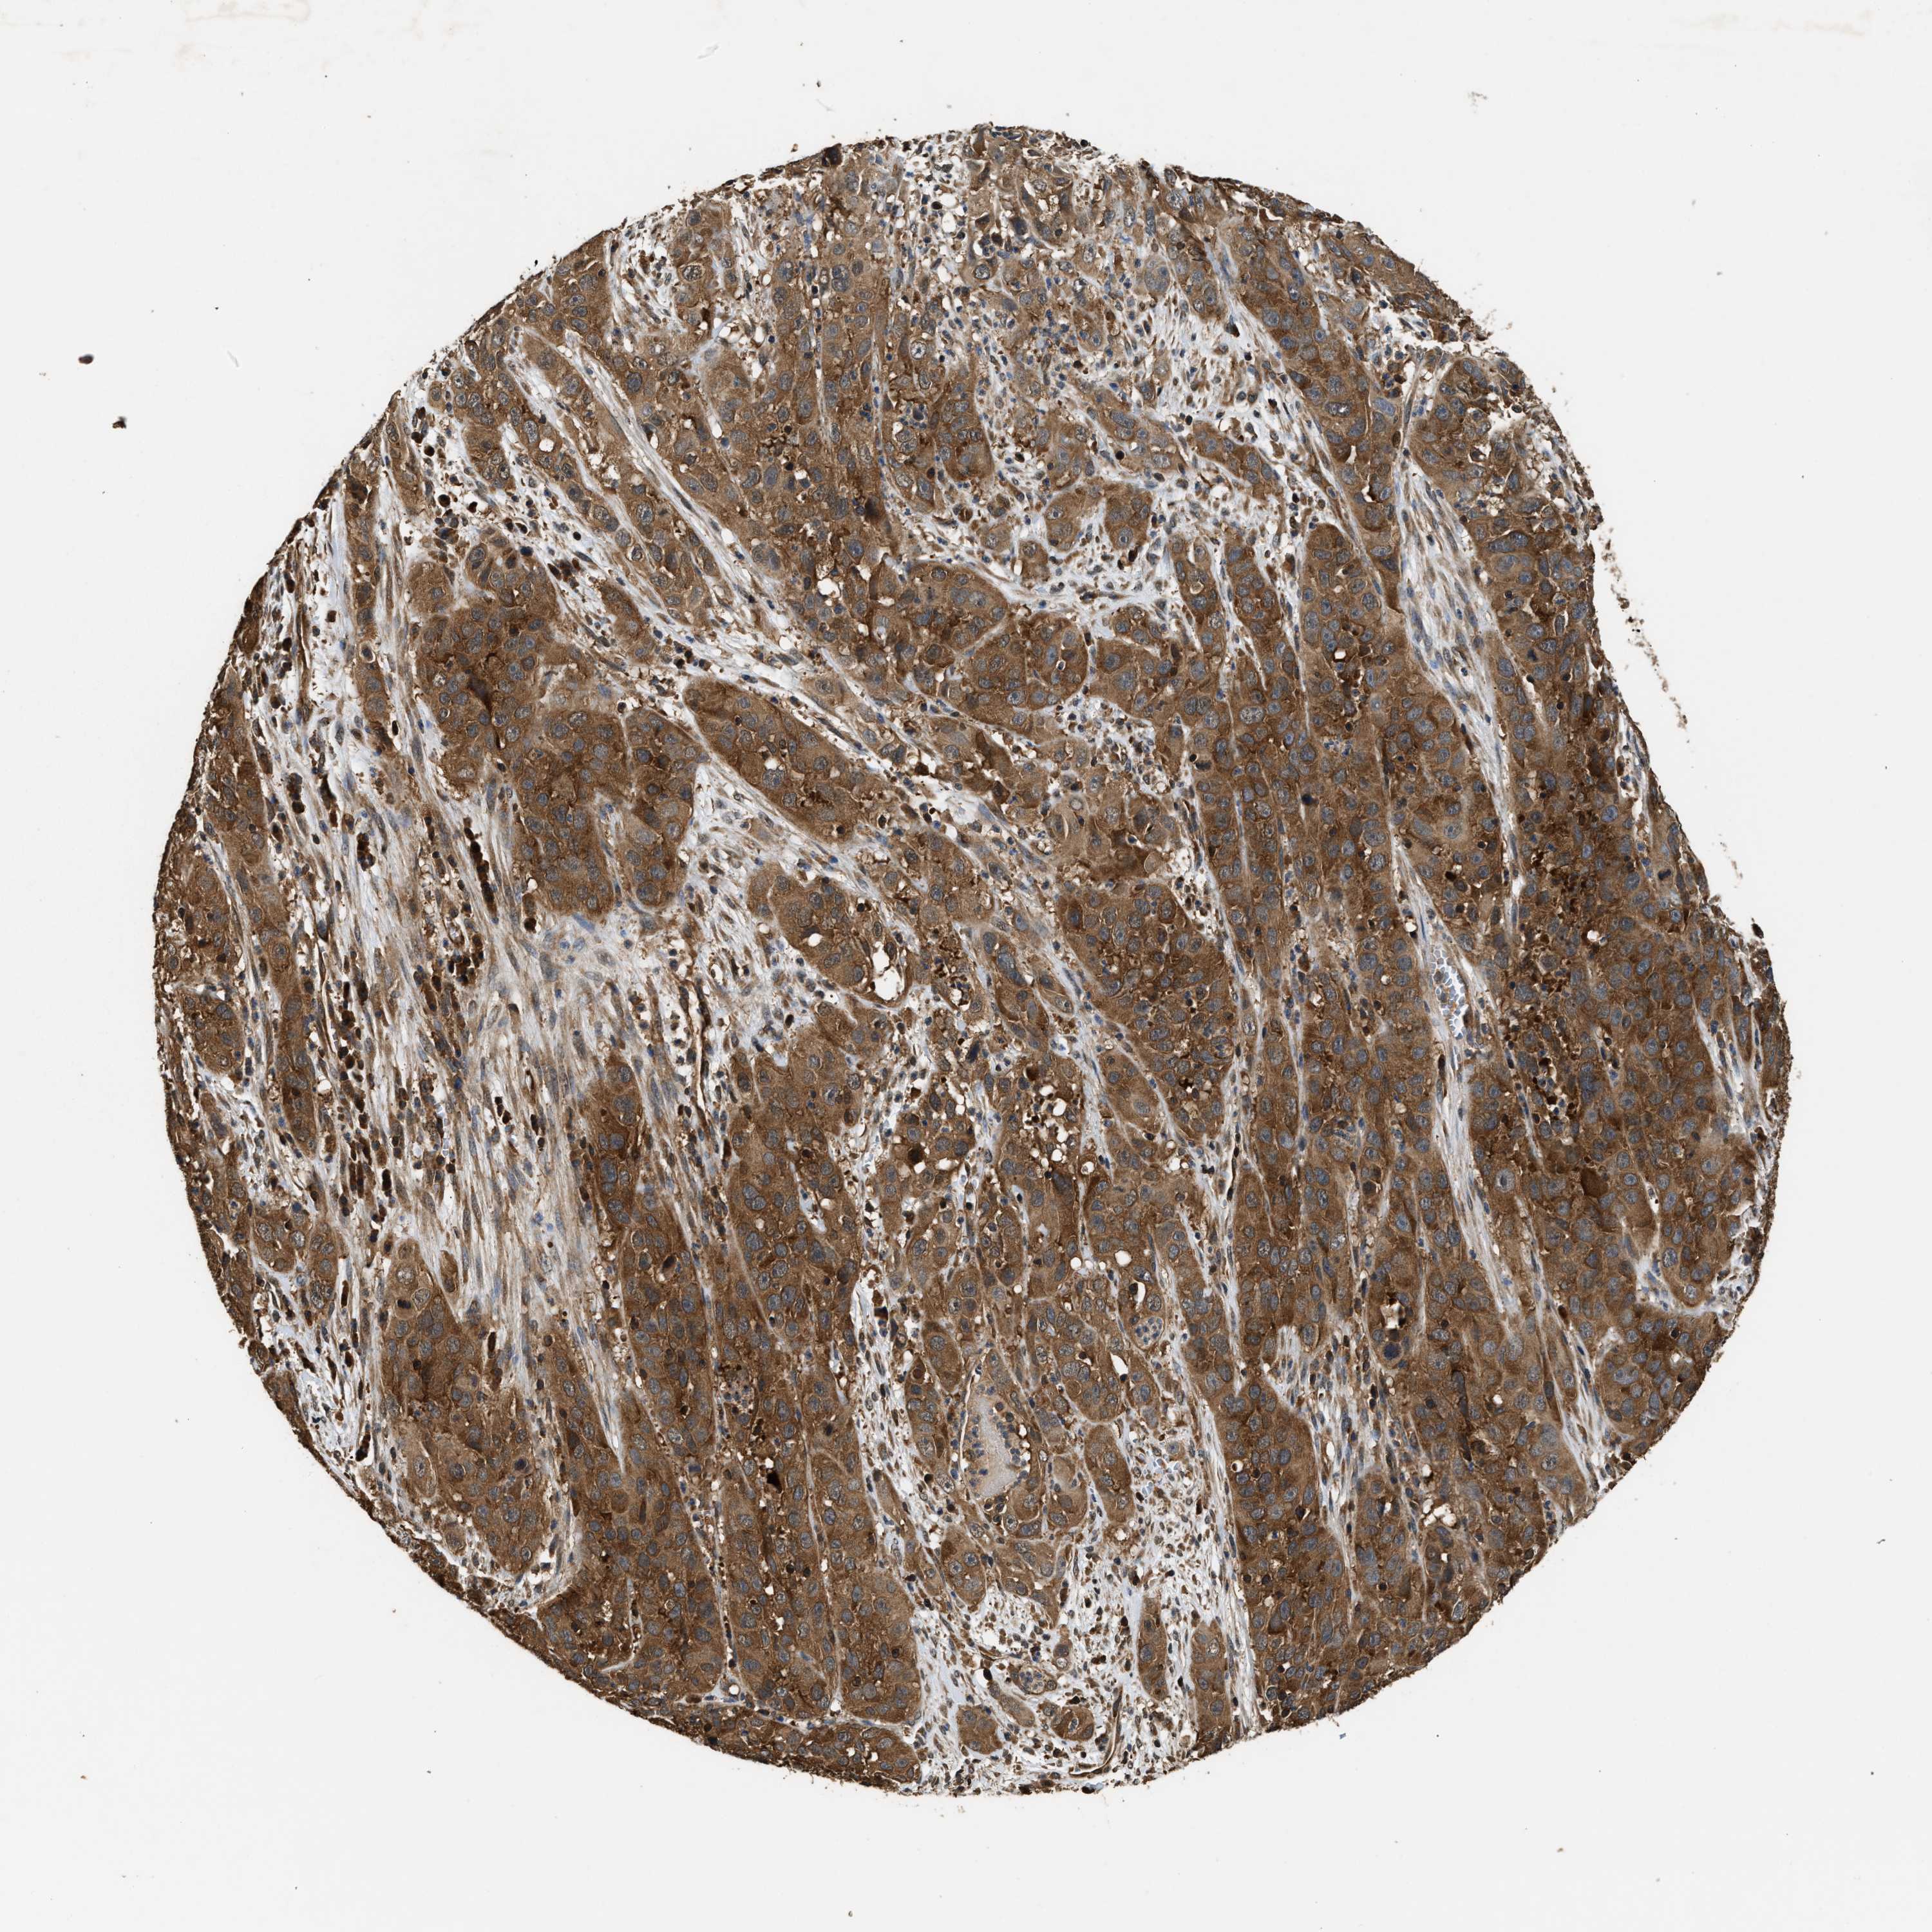

CERVICAL CANCER - Protein expressioni

A mouse-over function shows sample information and annotation data. Click on an image to view it in a full screen mode. Samples can be filtered based on level of antibody staining by selecting one or several of the following categories: high, medium, low and not detected. The assay and annotation is described here.

Note that samples used for immunohistochemistry by the Human Protein Atlas do not correspond to samples in the TCGA dataset.

Antibody stainingi

Antibody staining in the annotated cell types in the current human tissue is reported as not detected, low, medium, or high, based on conventional immunohistochemistry profiling in selected tissues. This score is based on the combination of the staining intensity and fraction of stained cells.

Each image is clickable and will lead to virtual microscopy that enables deeper exploration of all samples and also displays staining intensity scores, fraction scores and subcellular localization as well as patient and tissue information for each sample.

Antibody HPA020454

Staining

High

Medium

Low

Not detected

Intensity

Strong

Moderate

Weak

Negative

Quantity

>75%

75%-25%

<25%

None

Location

Nuclear

Cytoplasmic/membranous

Cytoplasmic/membranous,nuclear

Squamous cell carcinoma, NOS

Adenocarcinoma, NOS